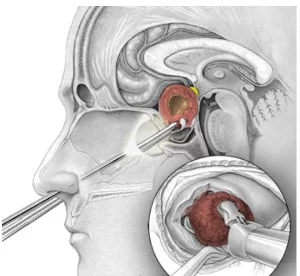

- Αφαίρεση του όγκου σε μικρά τεμάχια με ειδικά, μακριά εργαλεία (εικόνα 3). Αρχικά αφαιρείται το κεντρικό τμήμα του όγκου (εσωτερική αποσυμπίεση) και στη συνέχεια παρασκευάζονται τα όρια του όγκου με τον εγκέφαλο. Μετά την αφαίρεση όλου του όγκου, ο χειρουργός προωθεί το ενδοσκόπιο στο εφίππιο για επιθεωρήσει για τυχόν υπολλείμματα. Μερικοί όγκοι αναπτύσσονται πλαγίως στον σηραγγώδη κόλπο και μπορεί να είναι δύσκολο να αφαιρεθεί εντελώς αυτό το τμήμα του όγκου χωρίς να προκληθεί βλάβη στα νεύρα και τα αγγεία. Αν μείνει πίσω όγκος, μπορεί να αντιμετωπιστεί αργότερα με ακτινοβολία/ακτινοχειρουργική. Ο χειρουργός φροντίζει ένα τεμάχιο του όγκου να σταλεί για βιοψία.